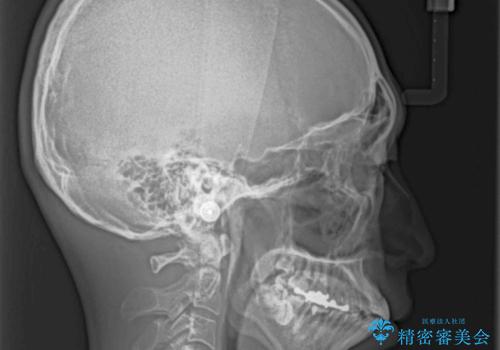

精密検査の結果、上下左右の小臼歯4本を抜歯し、そのスペースに前歯を後方へ移動させる矯正治療をご提案しました。

治療期間は約2年。

少しずつ前歯を後ろに下げていくことで、横顔のラインが整い、口元の“出っ張り感”が解消。